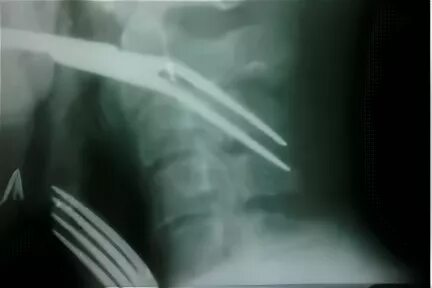

Как достать косточку из горла